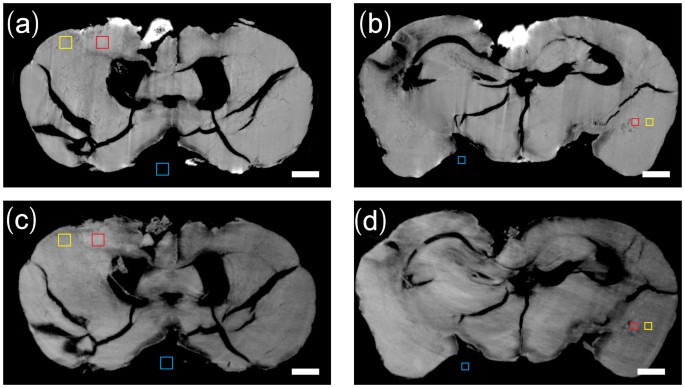

In order to quantify the visibility difference of the metastases by two techniques, we performed a CNR (Contrast-to-noise ratio) analysis in the selected homogeneous ROIs (region of interest) in each slice. We chose three regions including 1) the tumor (red square), 2) the surrounding region of the tumor (yellow square) and 3) the background region (blue square) in Fig. 3. ROIs with an areas of 200 × 200 μm2 were chosen for motor cortex micrometastasis and ROIs with areas of 120 × 120 μm2 for hippocampus micrometastasis. The CNR is calculated as follows:

where M1 and M2 are the mean δ value of region (1) and (2), σ3 is the standard deviation of δ value in background region (3) which provides a measure of the image noise level. The uncertainty of the CNR was determined by standard error propagation method21. Table 1 lists the CNR of the ROIs in IPC and GPC. The CNR of GPC in motor cortex micrometastasis was 22.3% lower than that of IPC, while in the smaller hippocampus micrometastasis, the CNR of GPC was 267% higher than that of IPC.

Three regions selected in IPC-CT image (a, b) and GPC-CT iamge (c, d) for CNR analysis.

(1) red square: tumor (2) yellow square: surrounding region of the tumor (3) blue square: background region. The areas of the square regions in (a), (c) are 200 × 200 μm2 while 120 × 120 μm2 in (b), (d). Scale bar: 500 μm.